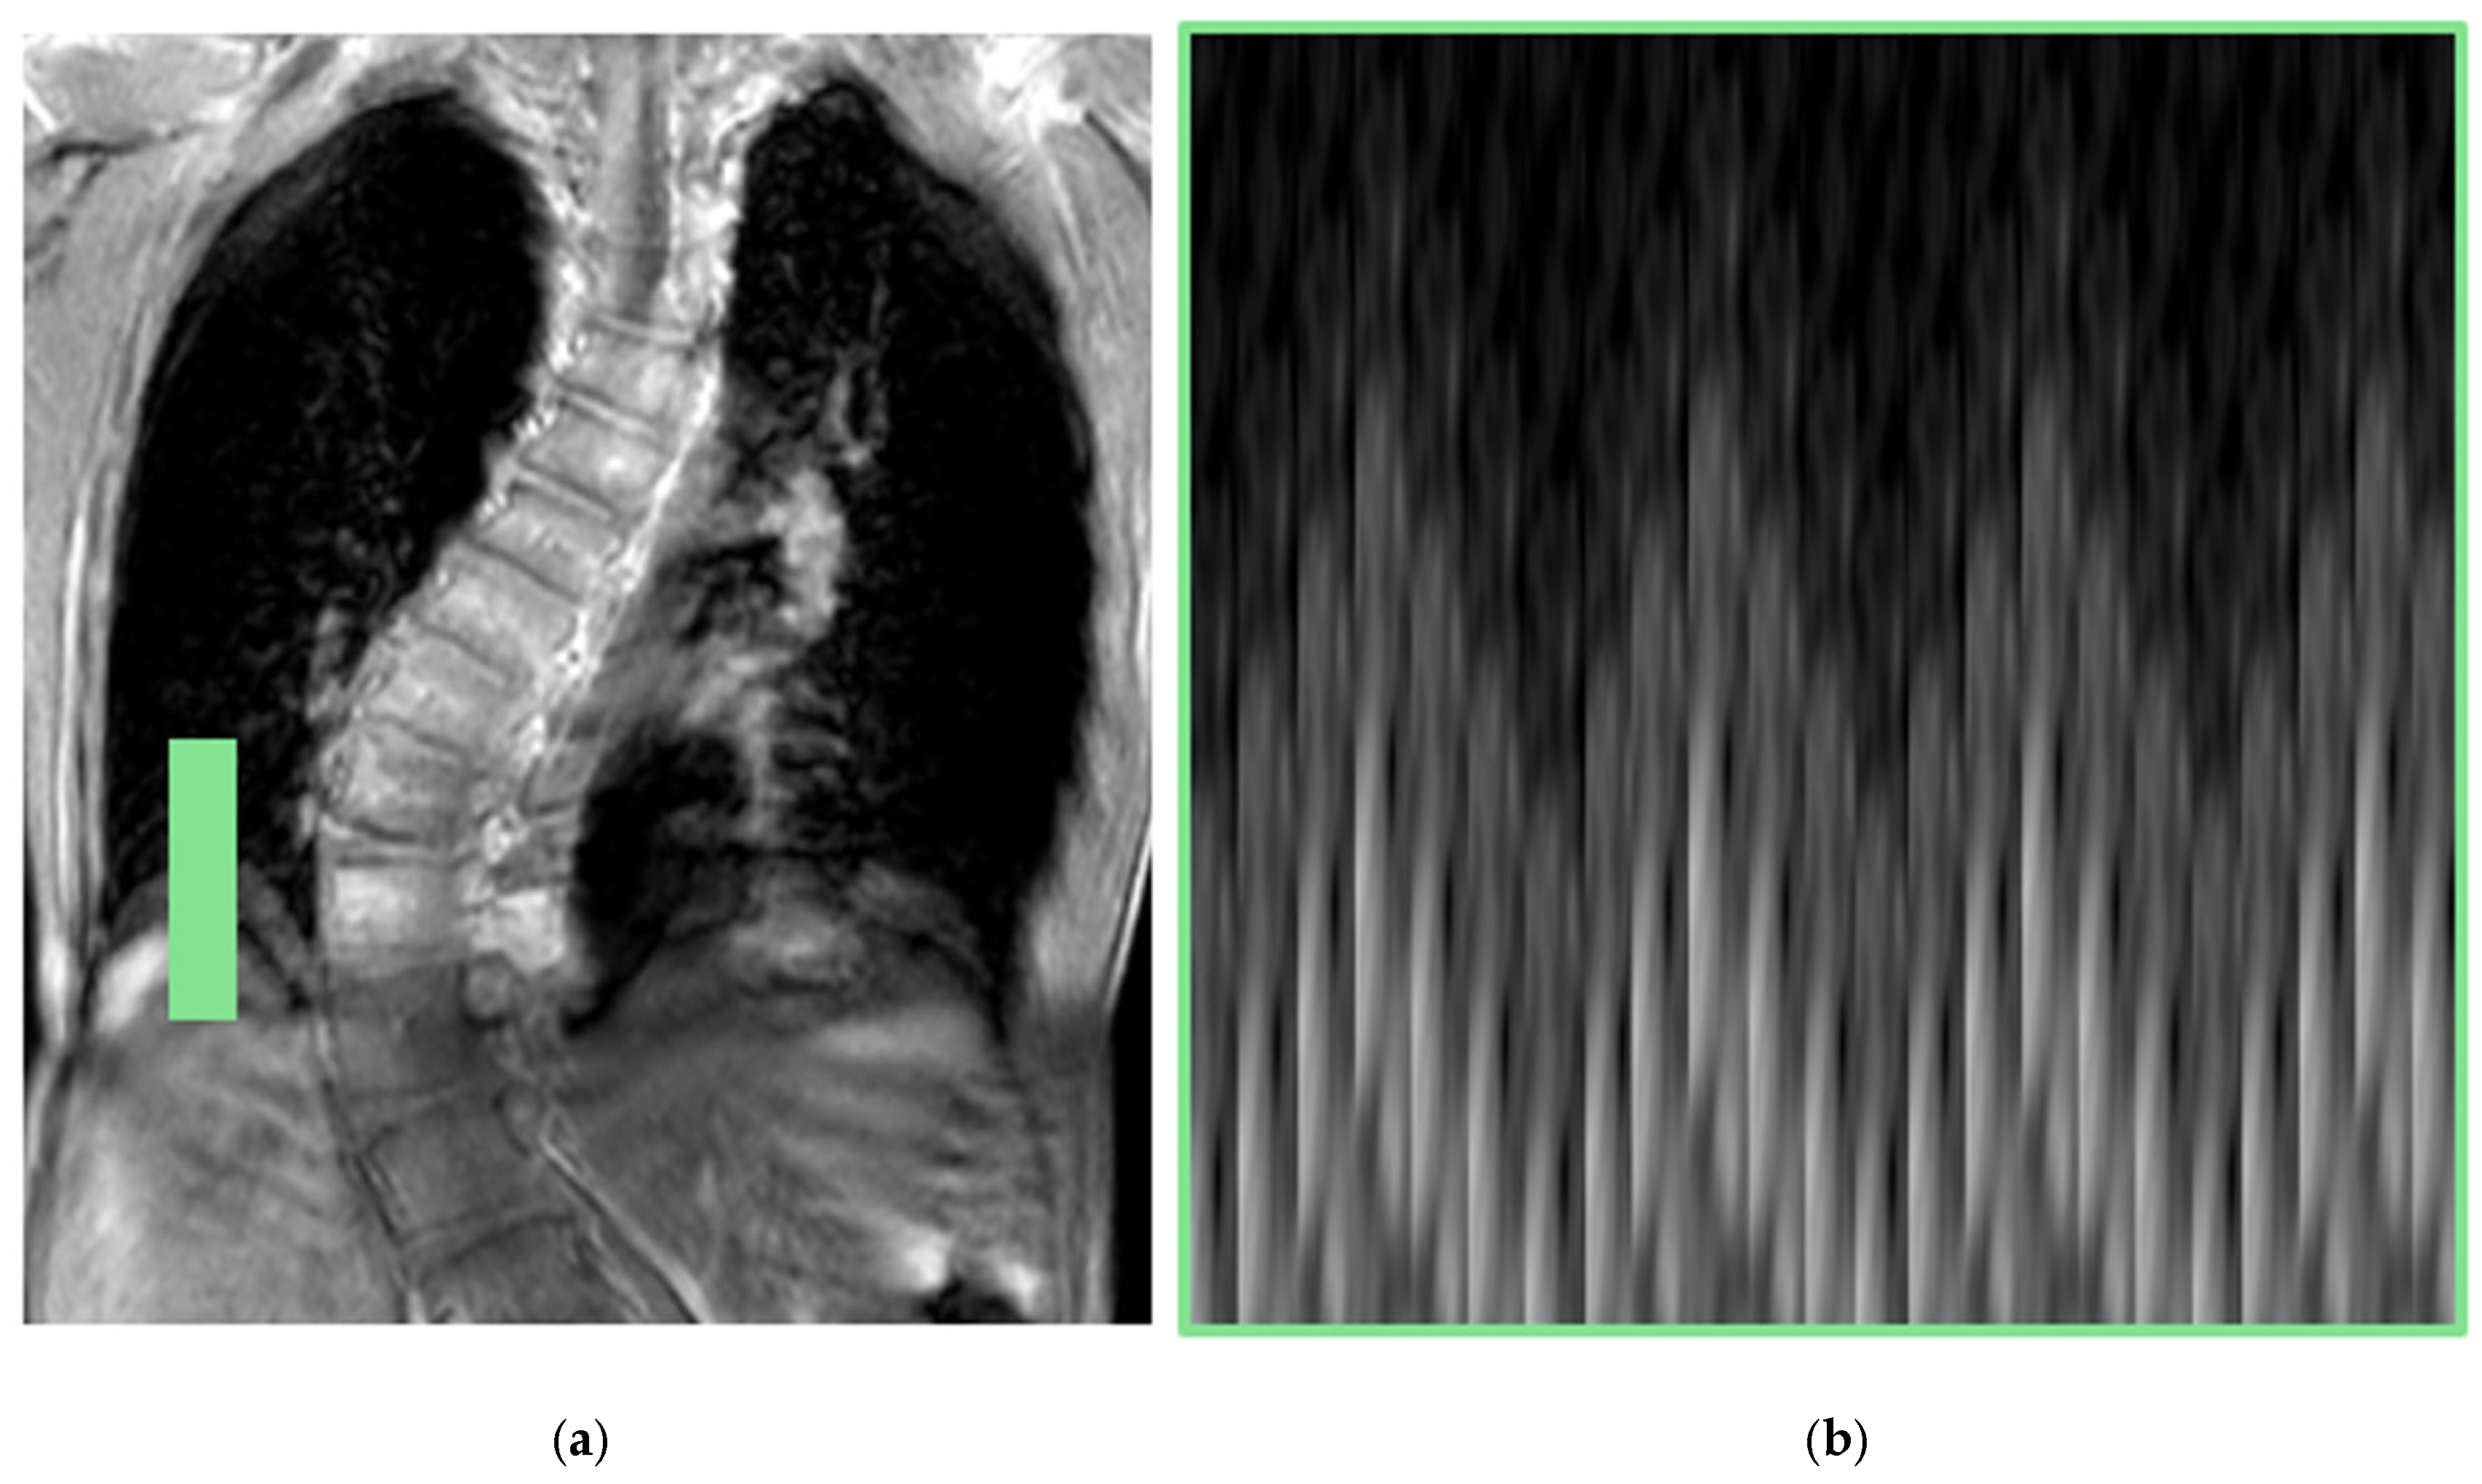

3.1.3. Four-Dimensional MRI